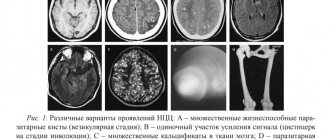

Эпидуральная гематома. КТ, аксиальный срез. Выпуклое гиперденсное образование, прилежащее к своду черепа. Швы служат естественным барьером для эпидуральных гематом, так как на этих участках твердая оболочка головного мозга плотно прикрепляется к своду черепа (а). Эпидуральные гематомы обычно возникают в области перелома (b).